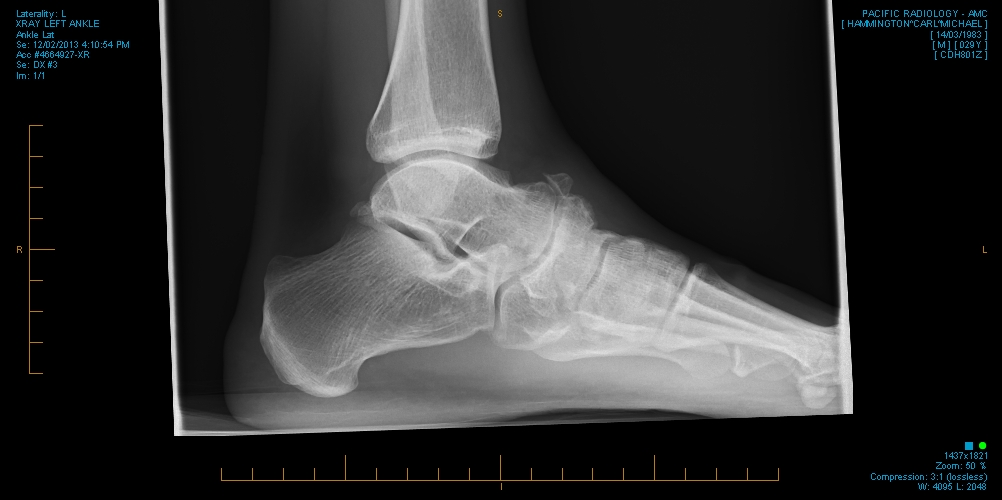

Oh yeah and apparently I have a broken ankle?! This definitely adds a new challenge to the trip…The amazing team at Willis Street Physiotherapy noticed something odd about my niggly ankle and referred me off to get an x-ray done. We are discussing options at the moment as we all know that it wont affect my participation in the race. I have already had one great acupuncture session that has helped minimise the discomfort 🙂